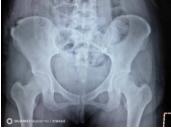

术后复查髂骨X线